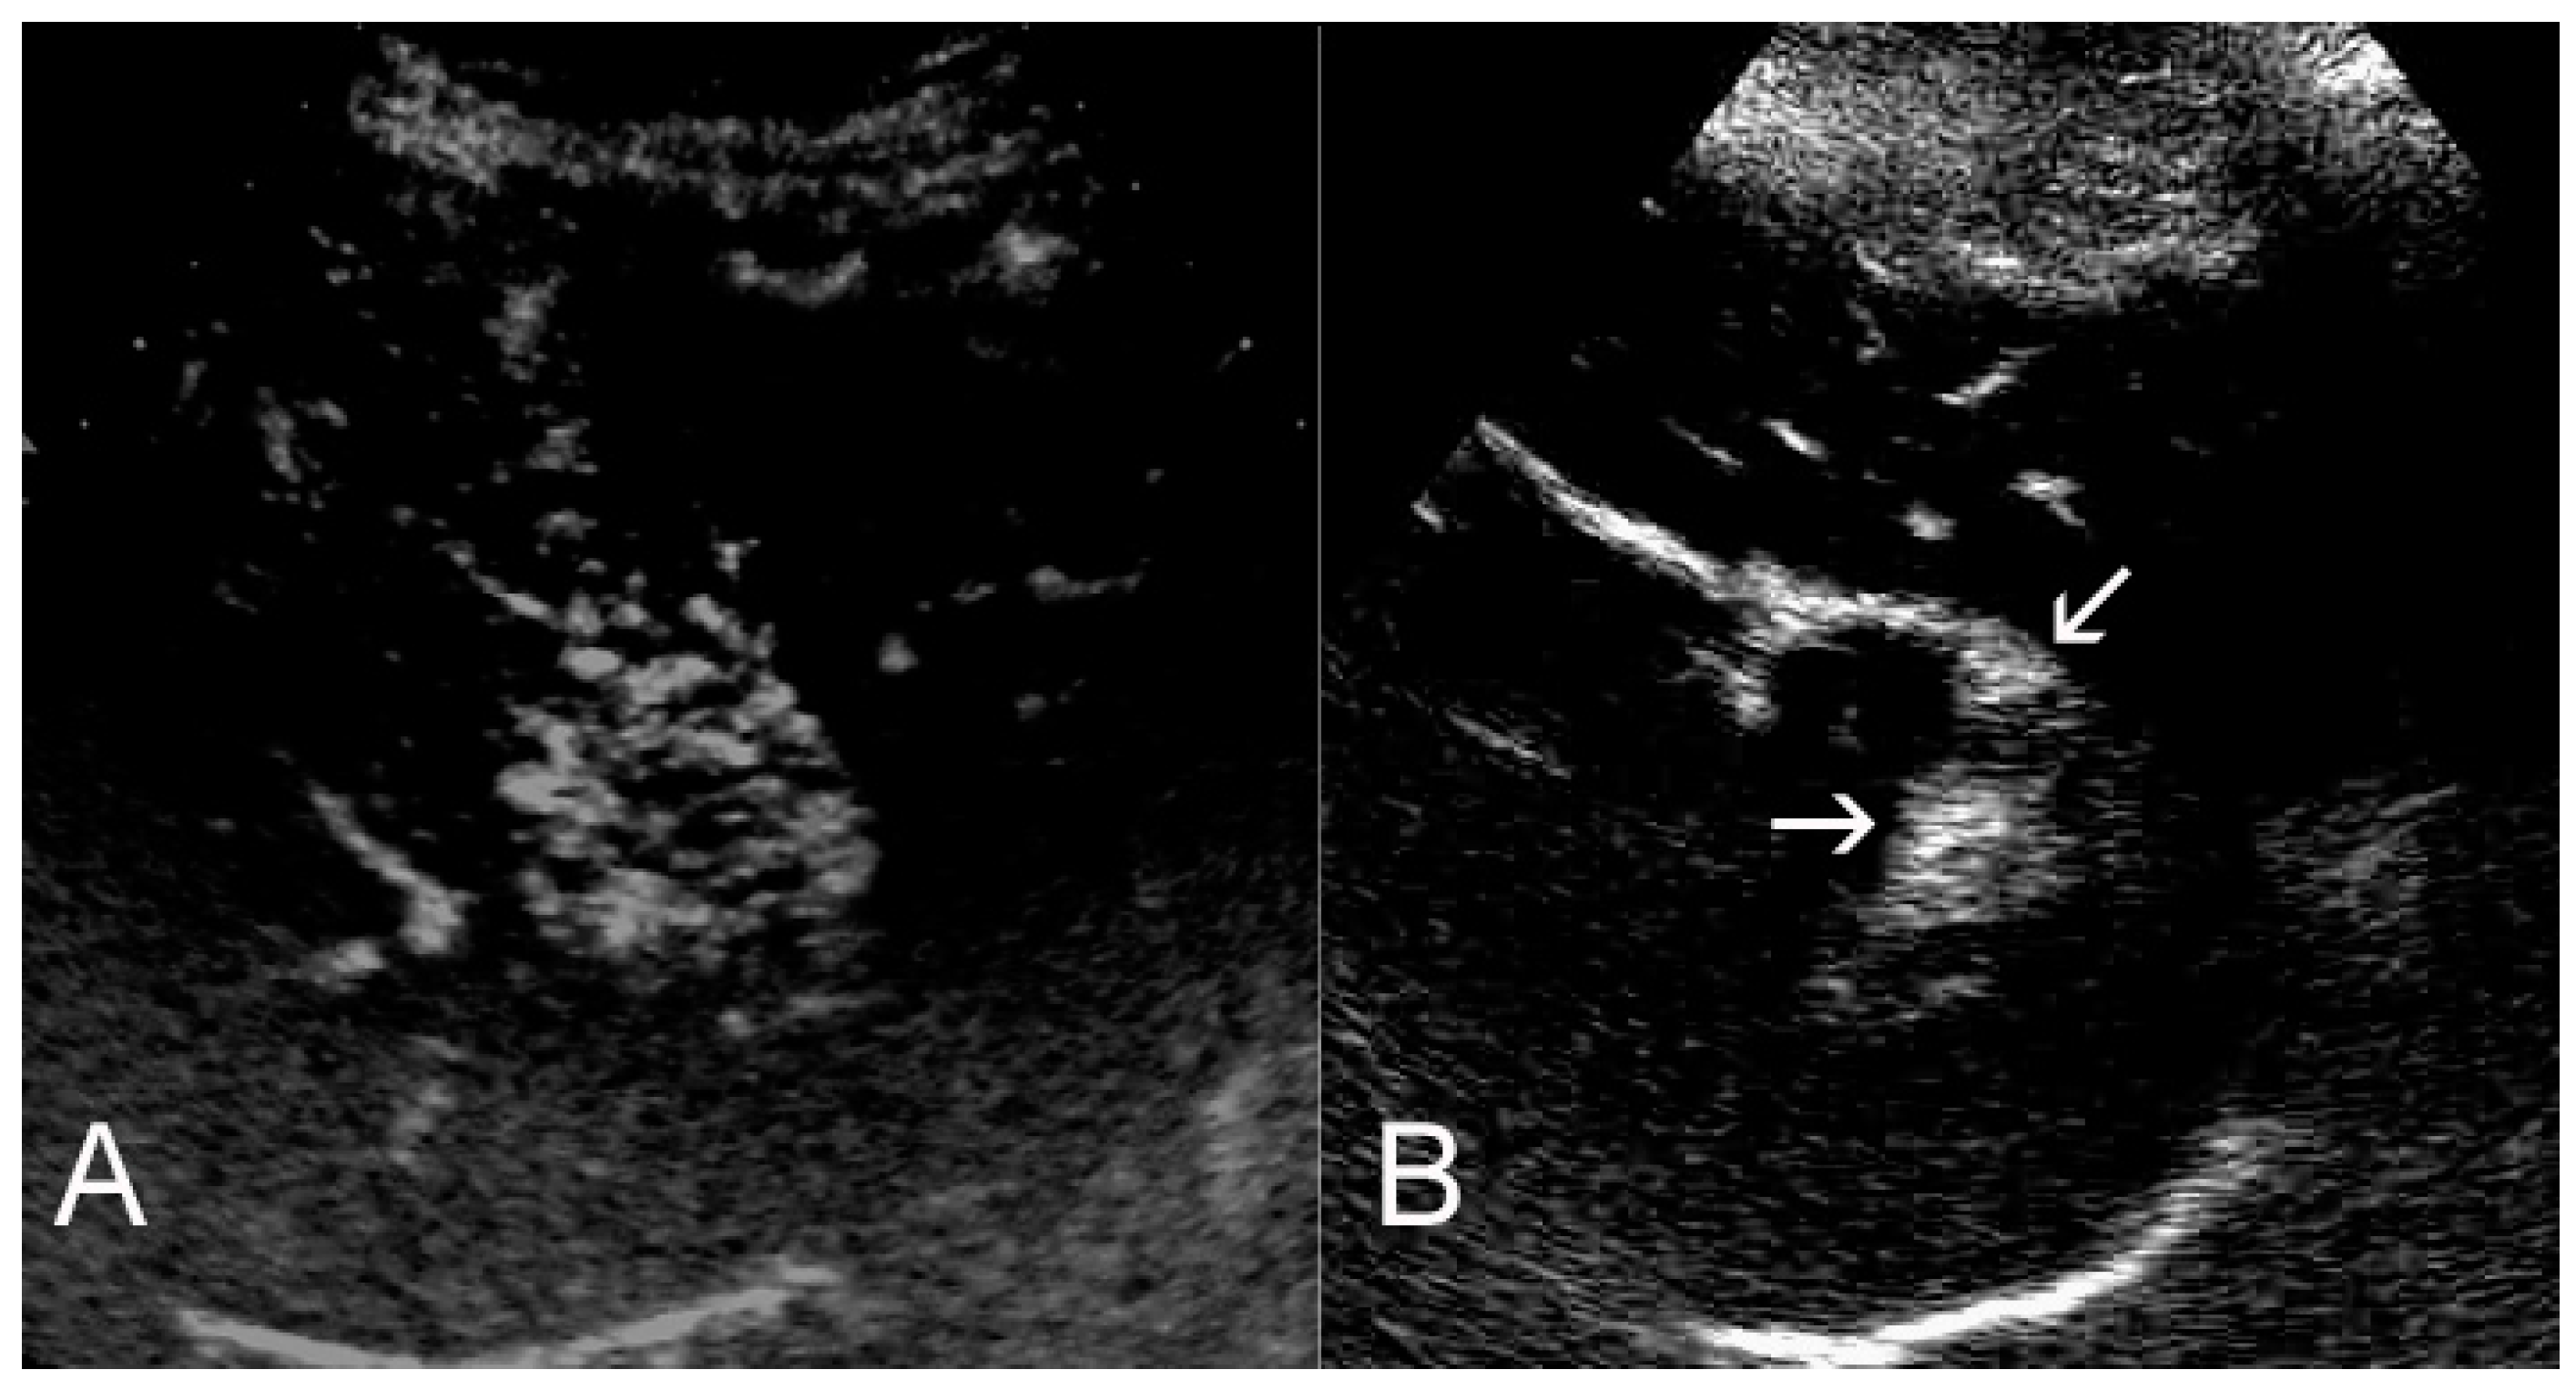

2. Assessment of Tumor Response

3. Ultrasounds